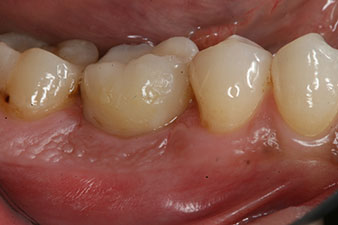

Fig. 1: Initial clinical situation after healing of extraction alveolus 36: The bone base is wide and there is sufficient keratinized gingiva.

A 28-year-old patient with a history of heavy smoking had to have tooth 36 extracted as a result of recurring apical periodontitis.

Due to the generally intact neighbouring teeth the only way to fill the gap was an implant.